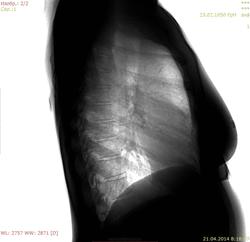

Пациентка 1950 г.р., отмечала повышение температуры до 39 градусов. Неспецифическая деструктивная пневмония в S6  или твс?

21/04/14

Пневмония,судя по положительной динамике.

Деструктивная? (кольцевидная тень)

В проекции переднего отрезка 4 ребра справа

Это скиалогия.

Присоединяюсь. Неспецифическая (недеструктивная) пневмония.